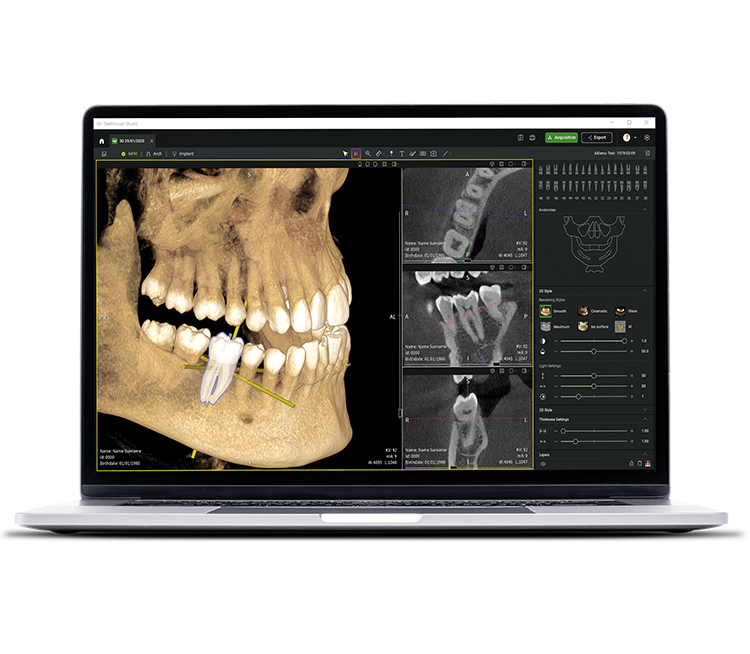

• Seethrough Studio

See tomorrow. See a new level.

In addition to sophisticated hardware technologies, the revolutionary Seethrough Studio software is a decisive factor for the high standard of the entire W&H imaging portfolio. With its beneficial features and advanced algorithms, Seethrough Studio is an all-in-one solution that takes imaging quality and digital dentistry workflows to a new level.

Seamless integration

Seethrough Studio can be easily integrated into your patient management system. You can start the software directly from the PMS without having to re-enter the patient data.

Free FOV selection on the scout image

Get the right image at the first scan: select the required FOV in the scout preview and freely adjust the region of interest. This ensures accurate positioning of the FOV and avoids the need to re-expose the patient.

Patient motion and position correction

The advanced patient motion correction algorithm elevates image quality to new levels in both 3D and 2D imaging. 2D images are further enhanced by a 21-layer autofocus system, seamlessly integrated with a patient positioning correction.

Metal artefact removal (MAR)

Restores image integrity by eliminating interference from metallic artefacts, and allows you to review images with MAR on or off – for a highly flexible visualisation and improved diagnostic accuracy.

Sharp, detailed and undistorted images

powered by the advanced algorithms of Seethrough Studio.

Implant planning tool integrated

In addition to the outstanding image quality and intuitive operation, Seethrough Studio offers numerous useful features such as the standard integrated implant planning tool for easy visualisation and preparation of the treatment.

AI-supported functions

Seethrough Studio utilises various AI tools for imaging enhancement, including 3D volume alignment, tooth segmentation, arch line generation, automatic nerve tracing as well as useful support for pathology detection.